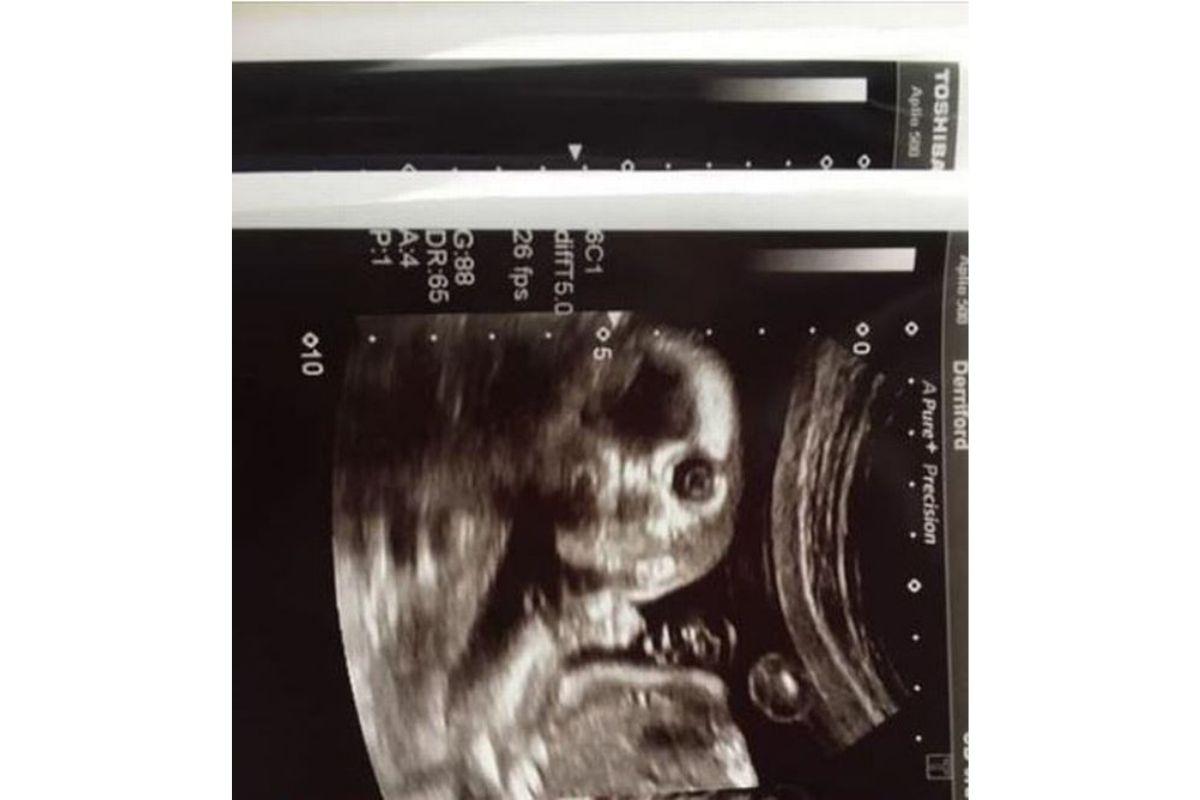

Joanne Greer, de 34 anos, deu um susto em todo mundo quando foi fazer um ultrassom de rotina às 20 semanas de gestação. Até a própria parteira ficou surpresa, afinal, a criança encarou a câmera e o momento foi registrado pelo hospital Plymouth, no Reino Unido.

De acordo com o jornal local Plymouth Live, a mãe contou sobre como tudo aconteceu: “Todos nós vimos as fotos padrão e fofas de lado, mas essa é nossa. É tão engraçado que quase nos molhamos de rir. A parteira riu e disse: ‘Isso não acontece com frequência”.

Que susto! (Foto: reprodução / Plymouth Live)

Em declaração, a família afirmou que usará a imagem na festa de 18 anos do aniversário do bebê, que ainda não teve o sexo revelado, pois a mãe decidiu saber apenas após o parto. “Acho que ninguém viu uma imagem digitalizada assim antes. Definitivamente, colocarei essa foto no cartão de aniversário de 18 anos da criança”, concluiu.